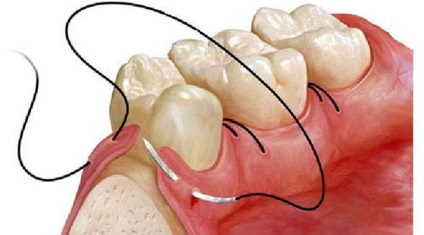

Când recesiunea gingivală în jurul dentiția este de asemenea folosit chirurgia lambou, numai pete de tesut guma nu se îndepărtează. Dimpotrivă, medicul efectuează o grefa de transplant dintr-o altă zonă. De exemplu, palatului moale. Acest clapă donator este conectat la zonele cu probleme, apoi capsate țesut. Din cauza un astfel de transplant este posibil să se complet închis la rădăcinile goale.

Dacă defectul este izolat și localizat numai într-un singur dinte, procedura este realizată în mod diferit. În buzunar parodontale face două orizontale și două crestătură verticală, după care un lambou de țesut gingival. Ei și aproape de rădăcină goale.